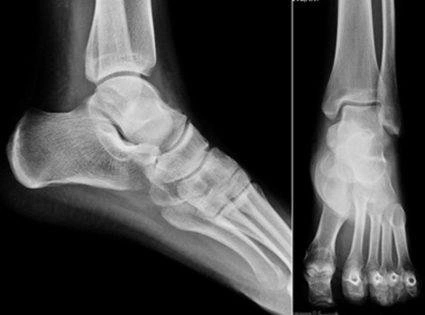

Стопа человека

Скелет человеческой стопы с пронумерованными пальцами

Cтопа человека является самым нижним отделом нижней части. Часть стопы, непосредственно соприкасающаяся с поверхностью земли, называется ступнёй или подошвой, противоположную ей верхнюю сторону называют тыльной стороной стопы. Стопа в целом имеет сводчатую конструкцию, не неподвижную, а благодаря сочленениями обладающую гибкостью и эластичностью. По костной структуре стопа делится на предплюсну